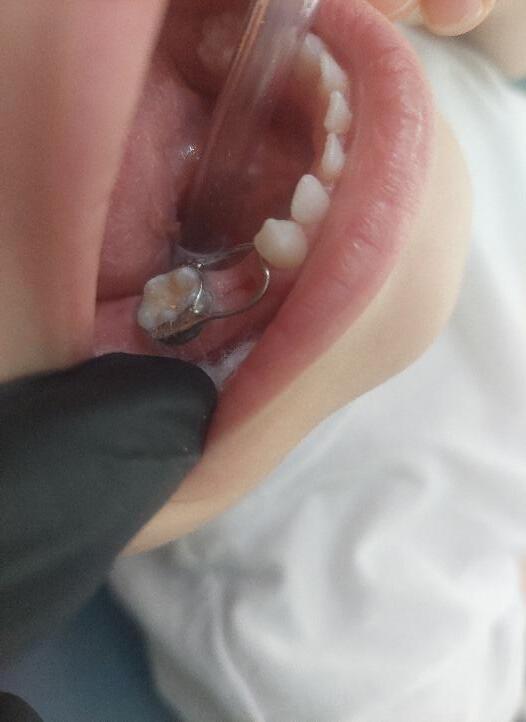

Γ2. Διατήρηση χώρου μετά την πρόωρη εξαγωγή νεογιλών οπισθίων δοντιών Σε περίπτωση πρόωρης εξαγωγής δοντιού (λόγω τερηδόνας ή αποστήματος) είναι απαραίτητη η τοποθέτηση μηχανήματος διατήρησης χώρου (space maintainer) μέχρις ότου

019

ανατείλει στο οδοντικό τόξο το μόνιμο δόντι. Αθλητικός νάρθηκας Διόρθωση οριζόντιας πρόταξης για αποφυγή οδοντικού τραύματος Η σημασία της στοματικής υγιεινής και ορθοδοντικής πρόληψης

020 Αν δεν διατηρηθεί ο χώρος της πρόωρης εξαγωγής, τα δύο παράπλευρα δόντια συγκλίνουν

τους,

το

δόντι παραμένει έγκλειστο ή ανατέλλει

Οι δεύτεροι προγόμφιοι ανέτειλαν υπερώια λόγω έλλειψης χώρου στο οδοντικό τόξο Η σημασία της στοματικής υγιεινής και ορθοδοντικής πρόληψης

μεταξύ

κλείνοντας τον χώρο και έτσι

μόνιμο

εκτός οδοντικού τόξου. Space

maintainer -band and loop μετά την πρόωρη εξαγωγή του 2ου νεογιλού γομφίου

Αυτό δημιουργεί και παράπλευρα προβλήματα στην σωστή σύγκλειση των δύο γνάθων με συνέπεια αισθητικά και λειτουργικά προβλήματα στα δόντια και στην άρθρωση των γνάθων (κροταφογναθική διάρθρωση ΚΓΔ).